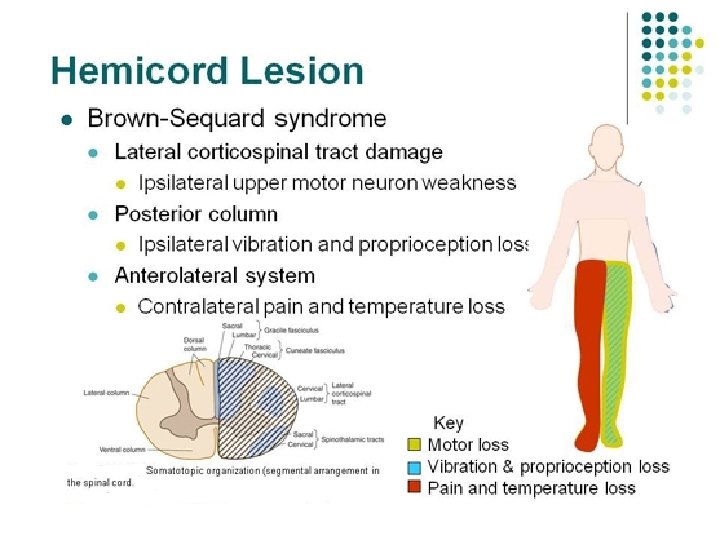

Localization of Lesion SPINAL CORD. Brown-Sequard syndrome (BSS) is a rare neurological condition characterized by a lesion in the spinal cord which results in weakness or paralysis (hemiparaplegia) on one side of the body and a loss of sensation (hemianesthesia) on the opposite side. Causes: • Trauma • Non-traumatic: Tumor (primary or metastatic), Multiple sclerosis, Disk herniation, Epidural hematoma, Vertebral artery dissection, Transverse myelitis, etc •